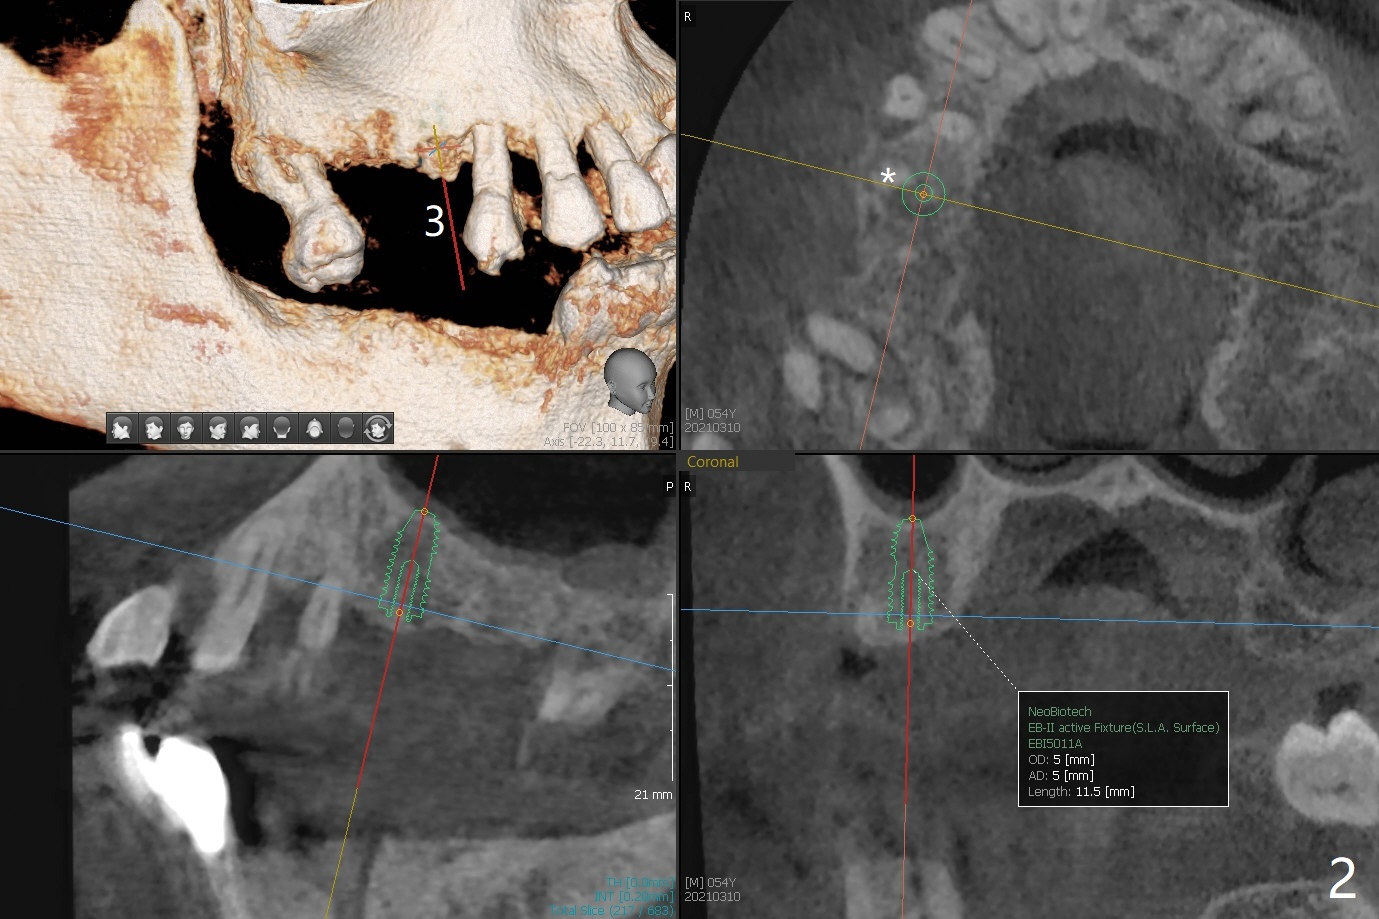

54岁男,28,29植骨后5个月,回来要求3,13,28,29种植(图一)。3号牙需要切开除去残根(图二:*),然后导板种植,准备两个PRF膜。为了保证植牙间距离,尝试在28,29处植入3.5x13毫米植体(图三,四)。在13号牙种植时(图五),考虑12号牙腭侧植骨(图六)。为了减少对12号牙咬合创伤,考虑4个植牙即刻修复。